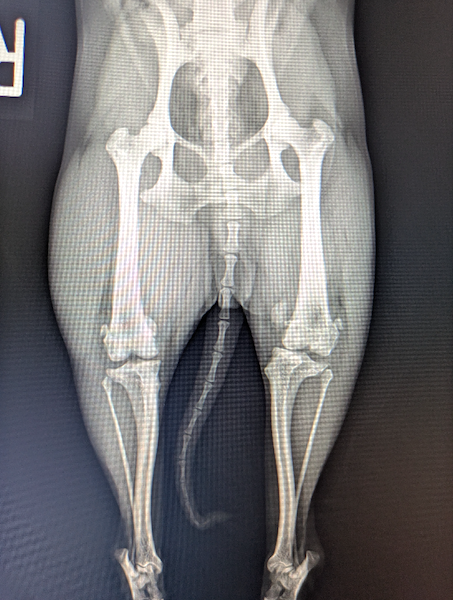

膝蓋骨脱臼(2024/12/18)

膝蓋骨脱臼は、小型犬に多く見られる運動器の病気です。膝のお皿が内側に外れる場合を内方脱臼、外側に外れる場合を外方脱臼と言いますが、内方脱臼の方が発生が多いことが知られています。症状としては、脱臼する側の後ろ足をあげる、足を地面に上手に着くことができないなどの歩行異常を認めます。この病気は自然に改善することはなく、特に成長期に病態が進む特徴があります。脱臼が頻繁に生じ、歩行異常や痛みの症状を認める場合、治療には骨格を矯正する外科治療が必要です。歩き方や座り方がおかしいなと感じる場合はお早めにご相談下さい。

獣医師 臼井